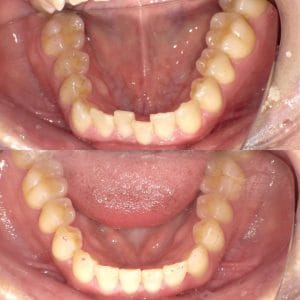

ワイヤー矯正

Case006 – ワイヤー矯正

片顎抜歯を行い、主に上の前歯の歯並びを矯正した症例です。

Case005 – ワイヤー矯正

Case004 – ワイヤー矯正

上下左右4本の抜歯を行い、全体の歯並びを矯正した症例です。

Case003 – ワイヤー矯正

Case002 – ワイヤー矯正

下の歯が前に出てしまう、いわゆる「受け口」を矯正した症例です。

Case001 – ワイヤー矯正